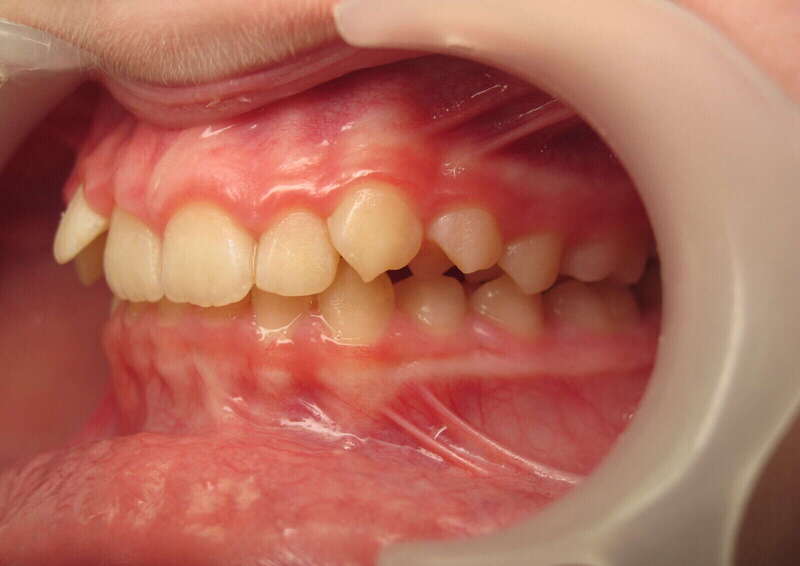

Cas n°1 traité par aligneurs - adolescent

Ce cas d’une adolescente illustre la correction d'une Classe II avec supraclusion par aligneurs. La stratégie thérapeutique a reposé sur une distalisation séquentielle de l'arcade supérieure. Ce mouvement précis a permis de reculer les dents maxillaires étape par étape pour annuler le surplomb (overjet) sans extractions.

Résultats clés :

• Correction fonctionnelle : Retour à un engrènement de Classe I stable et correction du recouvrement vertical.

• Esthétique restaurée : Harmonisation globale du sourire et du profil.

• Approche moderne : Un traitement discret, confortable et hautement prévisible.

Le résultat final montre une occlusion saine et un sourire parfaitement aligné, garantissant une santé dentaire et articulaire optimale pour l'avenir.

Avant

Après